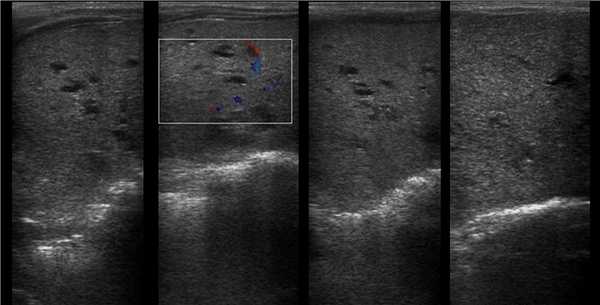

Рисунок 5 | Обе почки увеличены в продольном размере (правая 10 см и левая 9 см), с повышенной эхогенностью (за счет акустического усиления крошечных кист) и измененной кортикомедуллярной дифференцировкой.

Рисунок 6 | Печень с врожденным фиброзом и кистозными расширениями в правой доле.